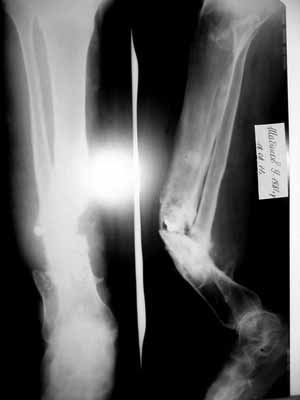

Ложный сустав костей левой голени

Травма в результате ДТП в 2004г., в анамнезе 4 операции

(АВФ, пластина, АВФ, фиксация винтом+ гипсовая лонгета(смысл не ясен)... )Мед. документацию по данному заболеванию больной не предоставил, всё со слов больного. Помогите определиться с тактикой лечения. Мы планируем произвести резекцию ложного сустава обеих костей левой голени, билокальный остеосинтез в аппарате Илизарова с компактотомией в/3 б/б кости. спс.

Добрый день. Мягкие ткани пациента конечно не в самом лучшем состоянии. Кожные покровы несколько гиперемированы, в п/о рубцах. Произведена резекционная секвестронекроэктомия обоих костей голени и фиксация в аппарате Илизарова. Укорочение конечности около 4,5 см. Кожные покровы не иссекли, ушили наглухо с дренированием.